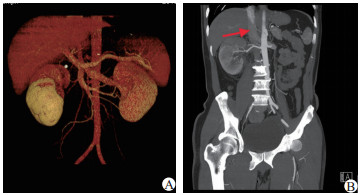

急诊医师予以解痉止痛后症状稍缓解。请泌尿外科会诊后考虑:1.急性肾绞痛;2.右侧输尿管结石?故转入泌尿外科治疗,行泌尿系统CTU示:1.右肾体积增大,右肾周、输尿管走行区周围脂肪间隙内多发渗出,右肾强化程度明显减低;2.CTU期右侧肾盂、输尿管未显影。患者目前检查无结石证据,但腰痛及血尿症状明显,暂不能排外肿瘤,故继续完善连续3 d尿脱落细胞学(后续结果:标本中见少量尿路上皮细胞,炎症细胞,未查见恶性肿瘤细胞)。继续行CTA(图 1)示:1.右肾静脉至下腔静脉血栓形成,右肾功能减低。2.右侧肾盂及输尿管壁增厚同前CT所示,周围渗出较前吸收。请肾内科会诊, 进一步查24 h尿蛋白定量为4.75 g/d(正常值0~80 mg/d),综合患者血白蛋白低,为24.7 g/L,诊断:肾病综合征。请血管外科会诊,建议抗凝治疗:伊诺肝素钠4 000 U/12 h皮下注射。抗凝一周后患者肌酐已降至正常。患者病情平稳后,转入肾内科治疗,予以正规疗程激素治疗:甲泼尼龙48 mg/d口服,补充人血白蛋白,并口服降脂药物、抗凝药物和胃黏膜保护剂。2个月后复查CT示:右肾体积较前明显缩小,右肾静脉显影良好,肾周以及输尿管周围渗出明显吸收,但左肾静脉内可见条状充盈缺损,血栓形成可能,下腔静脉显影良好,未见充盈缺损。

图 1 患者CTA结果(A:3D血管显像;B:箭头示右肾静脉血栓)